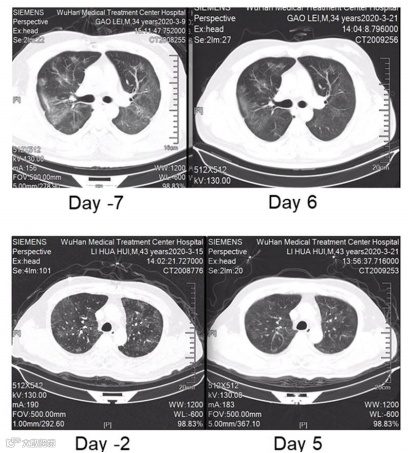

上海复旦大学华东医院及上海交通大学医学院瑞金医院等联合发表了一篇关于外泌体雾化吸入文章安全性及有效性的研究,对感染COVID-19的7名患者通过气溶胶吸入人脂肪来源的MSC (haMSC-Exos)外泌体进行治疗(图4)。7名重症COVID-19 相关肺炎患者(4名男性和3名女性)每日吸入haMSCs-Exos(2.0 × 108纳米囊泡),并保持连续5天的持续治疗。所有感染COVID-19 患者对haMSC-Exos雾化吸入的耐受性良好,雾化期间无不良事件或临床相关问题出现。7例患者中有4例肺部病变的消退明显,肺部CT成像显示双肺病变在治疗前后对比得到不同程度的改善。

图4 COVID-19患者吸入haMSC-Exos前后胸部CT扫描的变化